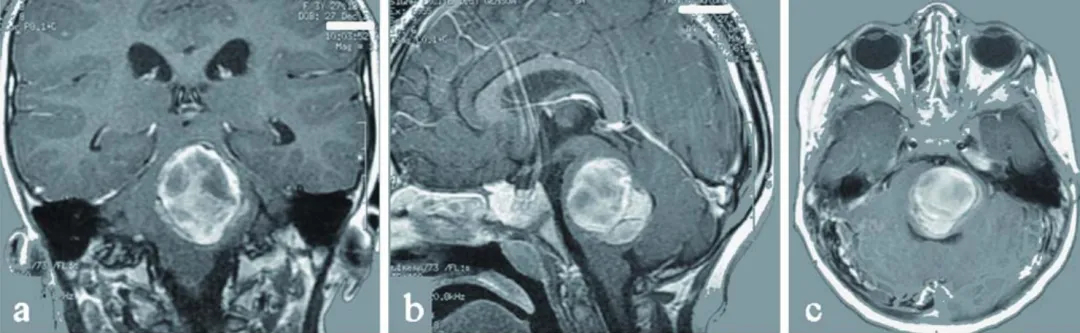

磁共振成像(MRI)给出了明确答案:脑桥位置有一个4×3.5×3cm的巨大海绵状血管瘤,同时大脑内还有多个额外病灶,其中左侧额叶的病灶已诱发癫痫,需药物控制。而这场危机的根源,正是脑桥病灶的增大与出血,持续压迫着关键神经中枢。

图a-c为术前影像